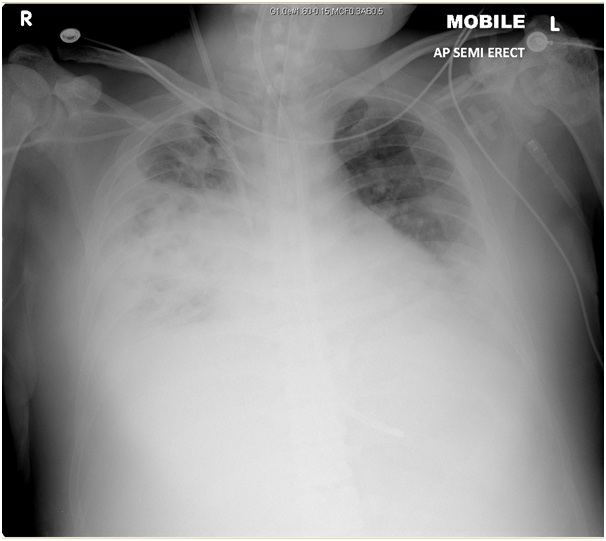

During his management in Accident and Emergency his clinical condition deteriorated rapidly with worsening cough and hemoptysis, his blood pressure dropped and developed clinical signs of septic shock. Patient was transferred to Intensive care unit where he was intubated & ventilated. He was started on vasopressor support, iv antibiotics and iv fluids. His admission bloods showed CRP 330, Creatinine 219, Urea 13.1, lactate 4.0, Bilirubin 31. His initial blood culture didn't grow anything. His throat swabs were positive for influenza B. His renal function deteriorated further and he was started on CVVH (continuous veno-venus hemofiltration) for acute renal failure. His malarial screen, urinary legionella & pneumococcal antigens came back negative. Repeat Chest X-ray showed worsening bilateral lung infiltrates.

Chest X-ray performed 2 days after admission, showing worsening bilateral lung infiltrates.